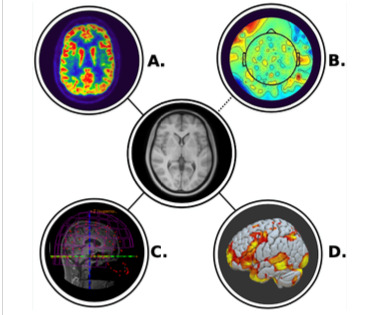

CAPSI will recruit 100 patients with cancer and depression that have an ongoing oncology clinic contact in Region Stockholm, Uppsala, Västra Götaland or Örebro during 2024-2026. Patients will be randomized to receive either psilocybin or an active placebo. Primary end point is depressive symptoms six weeks post dose. Follow up at six months. Potential side effects, various aspects of the therapeutic component and the health economic value of treatment will also be studied. In addition, all patients will submit blood samples and undergo EEG before and after treatment. All patients in Region Stockholm and Uppsala will also undergo MEG, fMRI and PET in order to understand psilocybin's mechanism of action in depression and to develop a marker that can provide a predictor model for psilocybin treatment response.